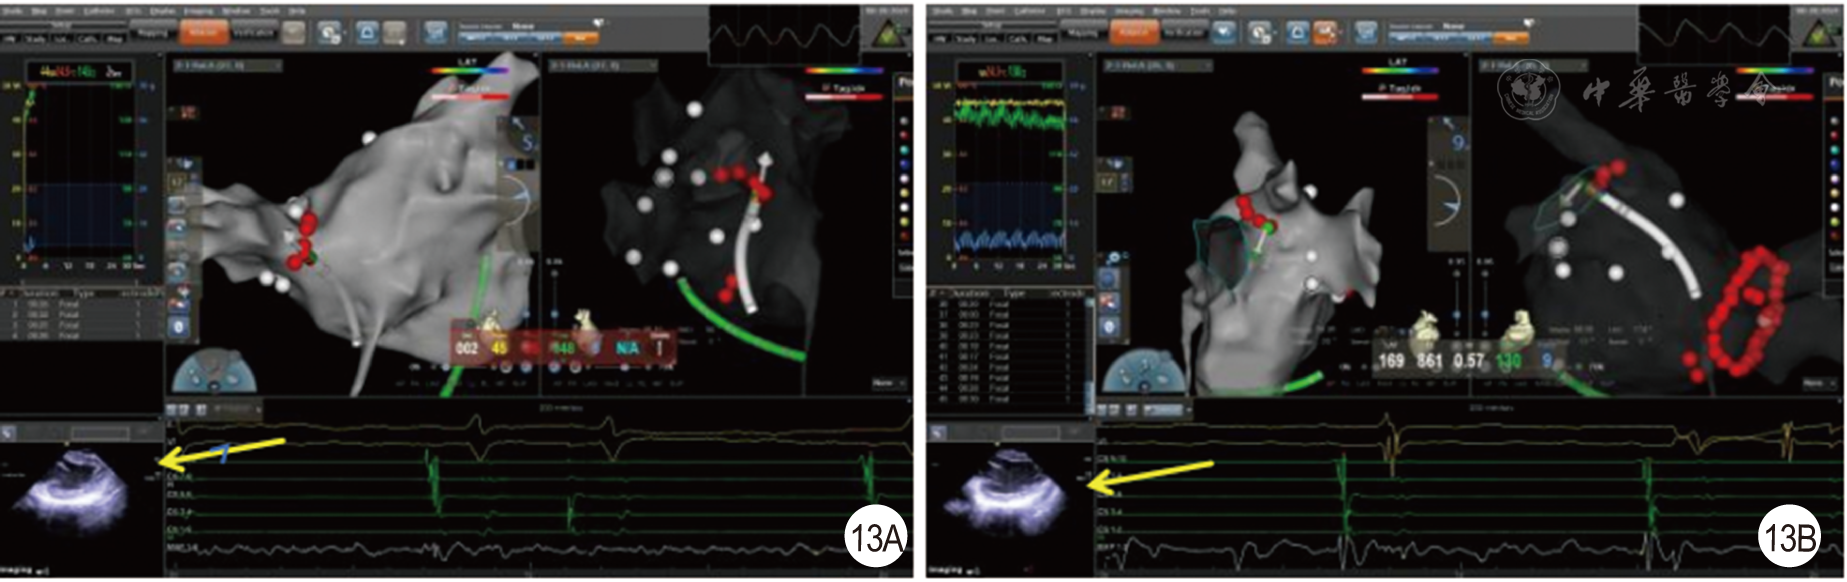

图13 心房颤动消融时,心腔内超声心动图(ICE)实时监测心包[13A为消融右侧肺静脉时ICE于左心室长轴监测心包腔(黄色箭头);13B为消融左侧肺静脉时ICE于左心室长轴监测心包腔(黄色箭头)]